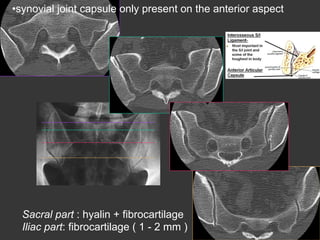

• synovial joint capsule only present on the anterior aspect

Sacral part : hyalin + fibrocartilage ( 2 - 5 mm )

Iliac part: fibrocartilage ( 1 - 2 mm )